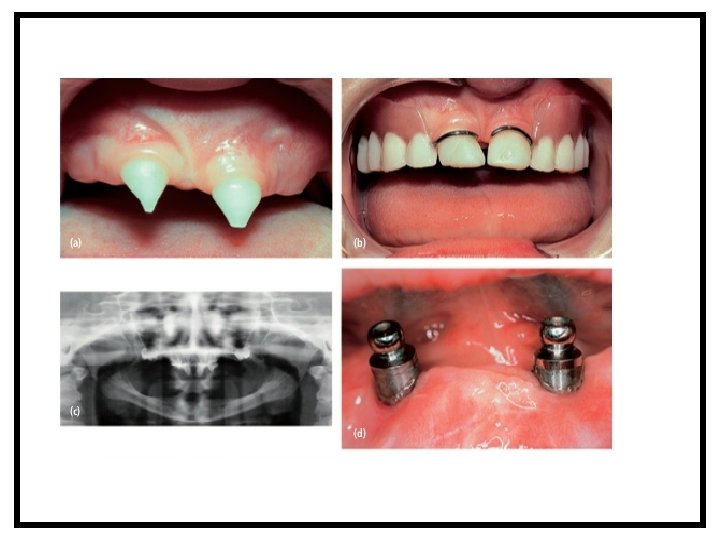

EKTODERMAL DİSPLAZİ OLGU 1 ED’li 5 yaşındaki hastanın klinik görünümü Lo Muzio L, Bucci P, Carile F, Riccitiello F, Scotti C, Coccia E, Rappelli G. Prosthetic rehabilitation of a child affected from anhydrotic ectodermal dysplasia: a case report. J Contemp Dent Pract. 2005 Aug 15; 6(3): 120 -6.

EKTODERMAL DİSPLAZİ OLGU 1 5 yaşındaki hastanın protetik rehabilitasyonu Lo Muzio L, Bucci P, Carile F, Riccitiello F, Scotti C, Coccia E, Rappelli G. Prosthetic rehabilitation of a child affected from anhydrotic ectodermal dysplasia: a case report. J Contemp Dent Pract. 2005 Aug 15; 6(3): 120 -6.

EKTODERMAL DİSPLAZİ OLGU 1 Olgu 1’in konik biçimli keser dişleri Olgu 1’in 7 yıl sonraki klinik görünümü Olgu 1 de konik keser dişlerin restoratif tedavisi Lo Muzio L, Bucci P, Carile F, Riccitiello F, Scotti C, Coccia E, Rappelli G. Prosthetic rehabilitation of a child affected from anhydrotic ectodermal dysplasia: a case report. J Contemp Dent Pract. 2005 Aug 15; 6(3): 120 -6.

EKTODERMAL DİSPLAZİ OLGU 1 Olgu 1’in protetik rehabilitasyonu Lo Muzio L, Bucci P, Carile F, Riccitiello F, Scotti C, Coccia E, Rappelli G. Prosthetic rehabilitation of a child affected from anhydrotic ectodermal dysplasia: a case report. J Contemp Dent Pract. 2005 Aug 15; 6(3): 120 -6.